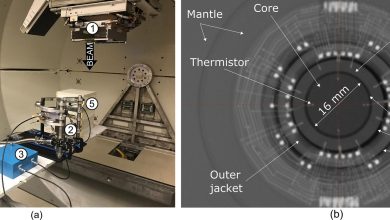

Configuração experimental montada na mesa do paciente e radiografia do NPL PSPC. (a) (1) Gantry, (2) NPL PSPC, (3) instrumentação…